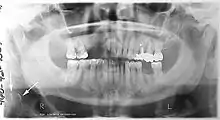

Atherosclerosis is attributed to risk factors that include cigarette smoking, hyperlipidemia, obesity, diabetes mellitus, and hypertension (high blood pressure). These factors, however, do not fully account for the risk of disease. Atherosclerosis has been conceptualized as a chronic inflammatory response to endothelial cell injury[24] and dysfunction possibly arising from chronic dental infection. In 2010, using the previously validated Mattila panoramic radiographic index to quantify the totality of dental infection (i.e., periapical and furcal lesions, pericoronitis sites, carious tooth roots, teeth with pulpal caries, and vertical bony defects), Friedlander’s group determined that individuals with carotid artery atheromas on their panoramic radiographs had significantly greater amounts of dental infection/inflammation than atherogenic risk-matched controls devoid of radiographic atheromas.[25][26] While the Mattila index had been previously used to relate the extent of dental infection to coronary artery disease, this research is the first to link the full range of dental disease that it measures to panoramic radiographs evidencing calcified carotid artery atherosclerosis.